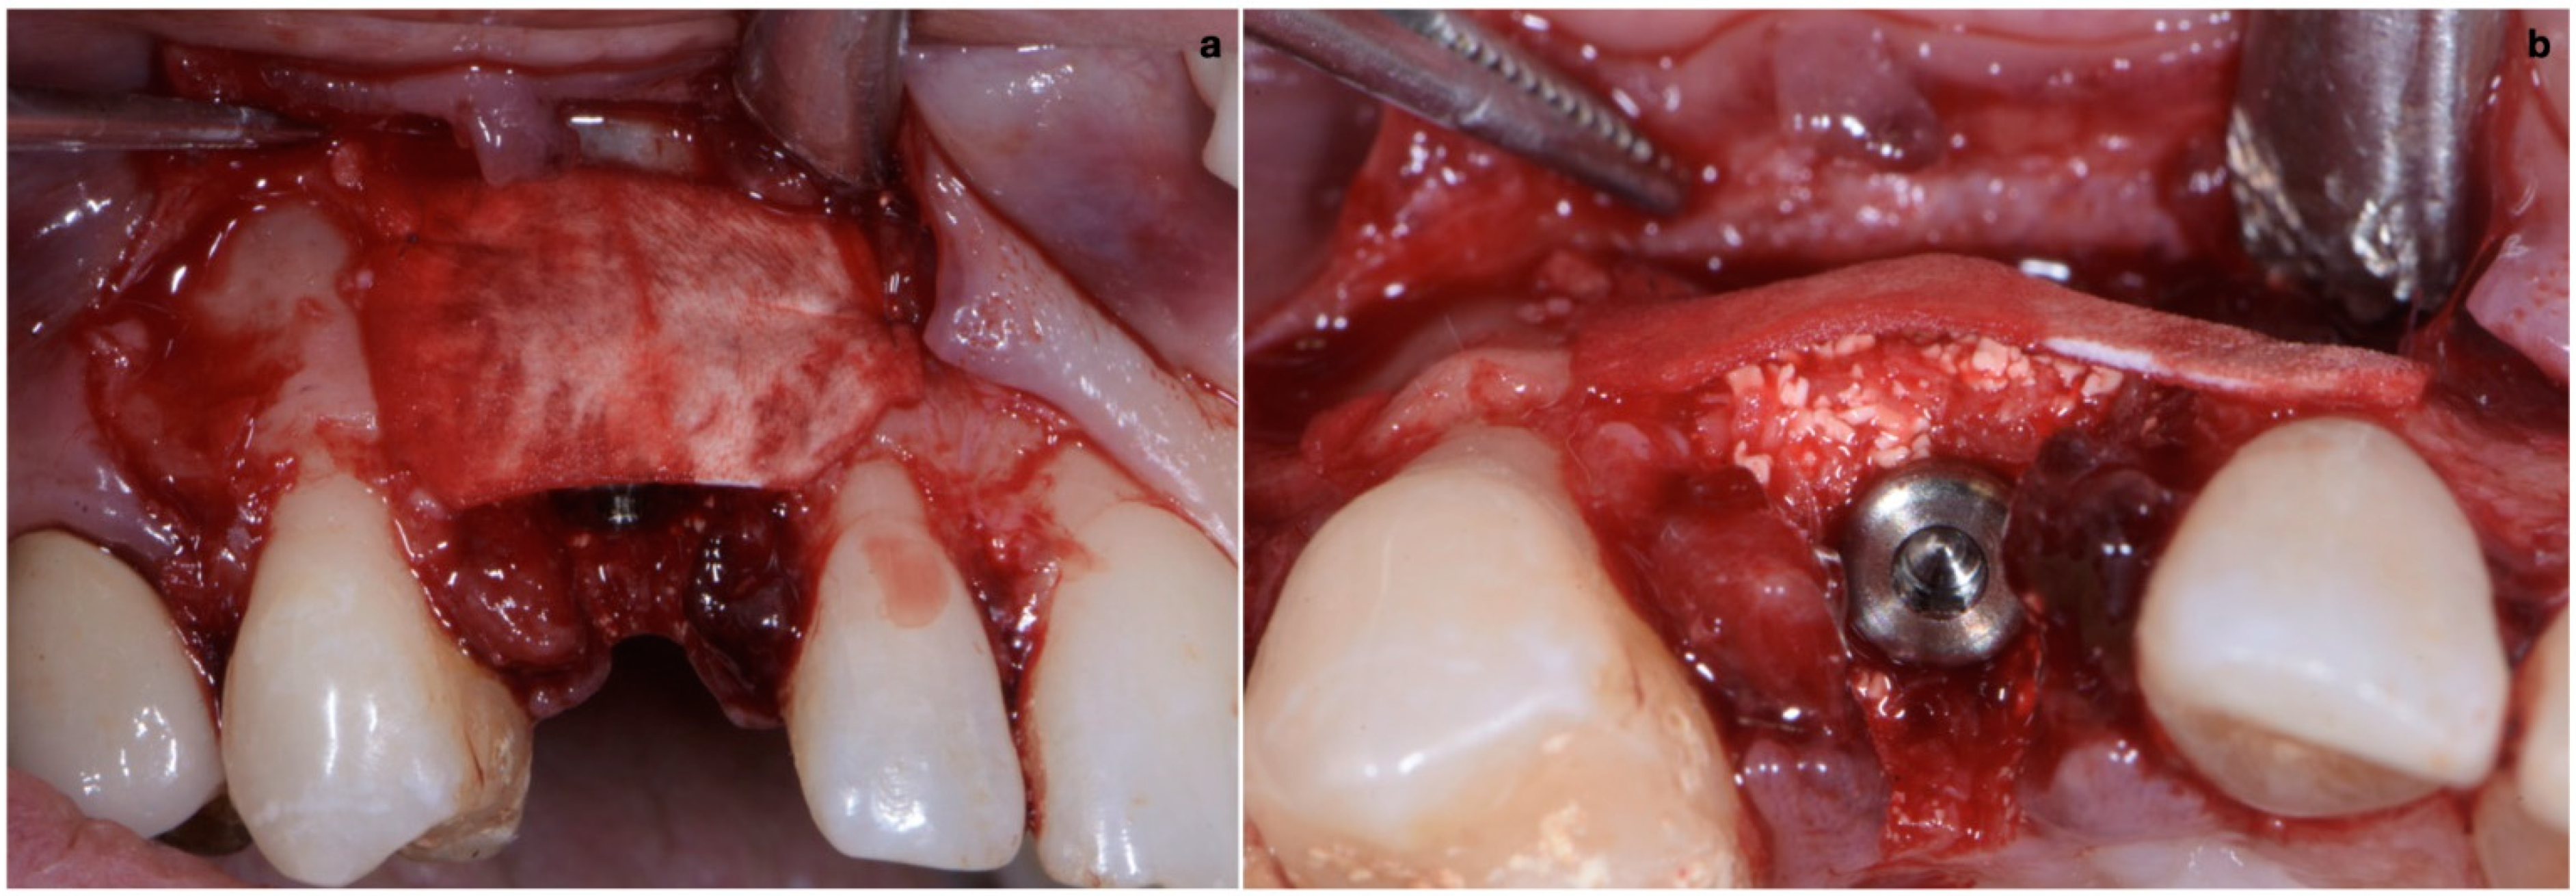

As already evaluated during software planning, after implant insertion, a buccal bone dehiscence of 2 mm occurred. The remaining buccal bone thickness was less than 1 mm. A mixture of biomaterial (Cerabone; Botiss) and autologous bone was placed to cover the exposed implant threads and the thin layer of remaining buccal bone and to fill the gap between the implant surface and the socket wall (Figure 7). Bone filler material should be limited to the rough implant surface, extending as little as possible to the transmucosal collar; however, the biomaterial positioning should be slightly in excess to avoid the loss of biomaterial during the following phase. If there is still an excess, it should be removed just before the very last suture. The biomaterial was then stabilized using a thin pericardium membrane (Jason Membrane; Botiss) placed between the bone particles and a connective-tissue graft (Figure 8a,b). The pericardium membrane was sutured to the periosteum left appositively laterally to the membrane.

The connective-tissue graft was harvested from the posterior palate as a free gingival graft and extra-orally de-epithelialized with a surgical blade, with attention paid to also removing glandular and fatty tissue [18]. The apico-coronal dimension of the connective-tissue graft was chosen by taking into consideration two reference points: the gingival margin of the contralateral tooth and the buccal bone crest. The graft should be sutured 1 mm coronal with respect to the ideal position of the mucosal margin, and it must be 2–3 mm apical with respect to the bone crest. The mesial distal dimension of the graft was extended to include the width of both papillae. This facilitated graft suturing and made peri-implant papilla growth in thickness and height possible. The graft was sutured in the inner aspect of the buccal flap 1 mm apical with respect to the mucosal margin with two horizontal internal mattress sutures (7/0 PGA thread; 8 mm needle) (Figure 9).

Figure 8. (a,b) Biomaterial stabilized by a thin pericardium membrane placed between bone particles and connective-tissue graft.